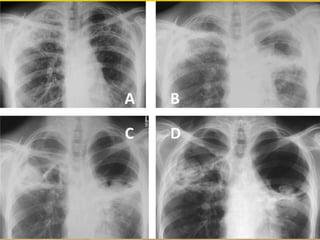

may appear nearly identical .Chest x-ray or CT scan

of the lungs can reveal haracteristic abnormalities.

aspergillosis diagnosed •Samples ofsputum, blood, or affected tissue can be cultured in the laboratory to grow aspergillus. •The fungus may be visible under a microscope in biopsies of affected tissue. Special stains for fungus may be needed, but other fungi may appear nearly identical .Chest x-ray or CT scan of the lungs can reveal haracteristic abnormalities. •A newer antigen-based test is available to detect evidence of invasive aspergillosis in the blood. However, the accuracy of this test appears to be variable.